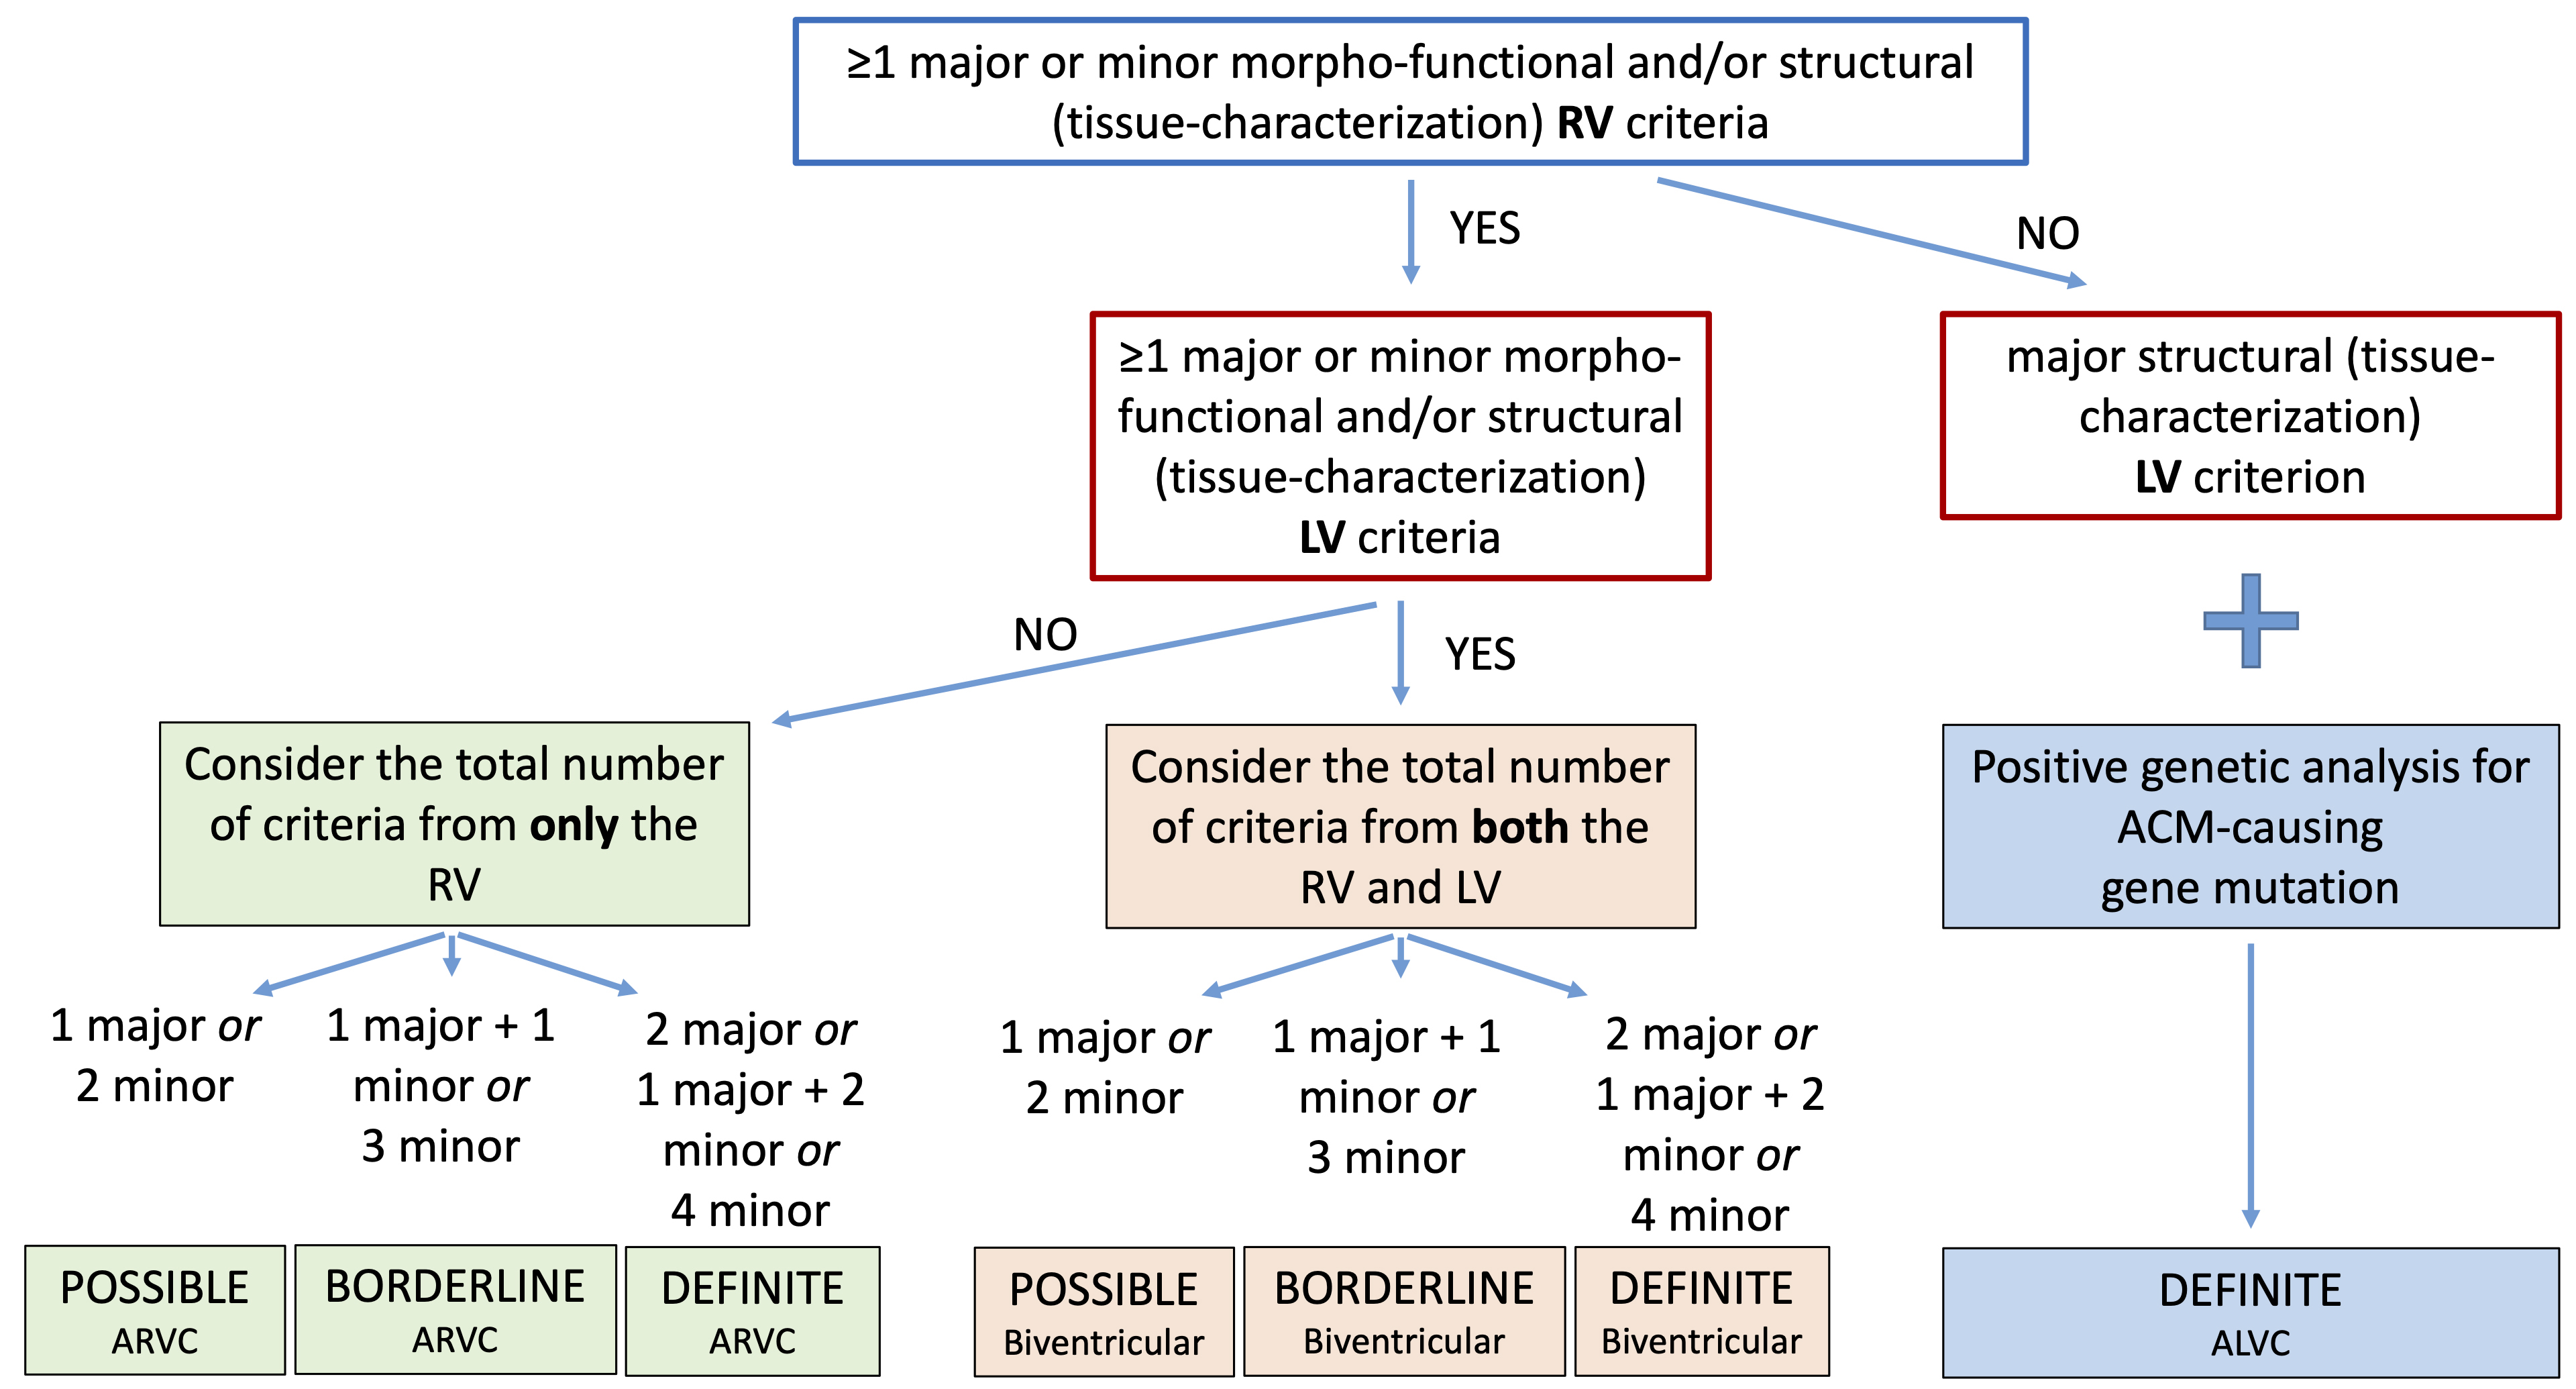

Finally, according to the number of LV and RV criteria that are fulfilled, the 2020 criteria provide a classification of ACM in three different phenotypic variants: “dominant right” variant, which is the classical form with RV involvement; “biventricular disease” variant, with involvement of both ventricles; “dominant-left” variant, with involvement of only the LV (Fig. 1, Ref. [20]).

Fig. 1.

Fig. 1.Flowchart for phenotypic characterization of ACM. The diagnosis of ACM requires at least 1 morpho-functional or structural abnormalities criterion, either major or minor. The diagnosis of the specific phenotypic variant depends on the ventricle interested on alterations (see text for details). Moreover, the likelihood of disease is defined by the combination of the major and minor criteria fulfilled. ACM, arrhythmogenic cardiomyopathy; ALVC, arrhythmogenic left ventricular cardiomyopathy; ARVC, arrhythmogenic right ventricular cardiomyopathy; LV, left ventricle; RV, right ventricle. Adapted from Corrado et al. [20].

The second step is the identification of the specific ACM phenotype according to the number of criteria for the RV and LV involvement that are fulfilled. According to the 2020 ITF criteria, any diagnosis of ACM requires that at least 1 criterion from category I (morpho-functional abnormalities) or II (structural abnormalities) must be reached, either major or minor, and only these two categories are taken into consideration to classify the phenotypic variant.

If these criteria are only fulfilled for the RV, the diagnosis is the classical right-dominant variant (ARVC). Whereas, if the criteria are fulfilled for both RV and LV, the diagnosis is “biventricular” form. Moreover, it is possible to define the likelihood of disease according to the number of major and minor criteria reached from all categories. So, the diagnosis can be “definite” if either 2 major criteria, or 1 major and 2 minor criteria or 4 minor criteria are fulfilled, “borderline” if either 1 major and 1 minor criterion or 3 minor criteria are reached, and “possible” if either 1 major criterion or 2 minor criteria are satisfied.

The diagnosis of ALVC is reached in patients with structural LV abnormalities (major criterion) and no RV involvement, when a pathogenic or likely pathogenic ACM-causing gene mutation is identified. In this case, the diagnosis of ALVC is always definite. The need for positive genotyping testing is due to the possible overlap of these morpho-functional and structural findings with phenocopies, such as DCM, cardiac sarcoidosis or myocarditis.